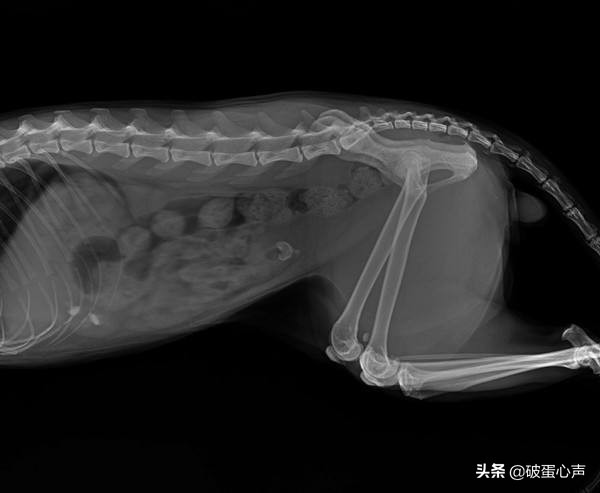

那么作为宠物的猫咪它们是否也会得膀胱炎?答案不可置疑是的,而且在泌尿系统的疾病里光是膀胱炎就占了大多数,那么应该怎么避免猫咪膀胱炎的发生呢?今天破蛋就给大家讲解一下膀胱炎的一些病因、症状、治疗以及预防的方法。

猫咪之所以会容易患有泌尿系统的疾病,其中储蓄尿液的膀胱发炎就是罪魁祸首。一般来说我们将膀胱炎分为“细菌性膀胱炎”和“特发性膀胱炎”。

细菌性膀胱炎是指细菌通过尿道、肾脏等地方感染到膀胱,使其发生炎症而出现膀胱炎;特发性(原因不明)膀胱炎则是指在没有细菌感染的前提下,因为一些其它的原因而出现膀胱炎。 在这里还需要补充一点的是,因为母猫的尿道比公猫的尿道要短,细菌就会更容易进入母猫的膀胱从而更容易引发膀胱炎。

而且猫咪是一种很敏感的动物,它们会对周围一些细微事物的改变而感到压力,继而就会容易引发膀胱炎;其次若是猫咪的日常饮食中含有太多矿物质的话,就可能会堵塞尿道而引发尿石症,尿石症继而也会导致膀胱炎;猫咪饮水量的不足才是引起膀胱炎的主要原因,到了冬季的时候也是膀胱炎的高发期。